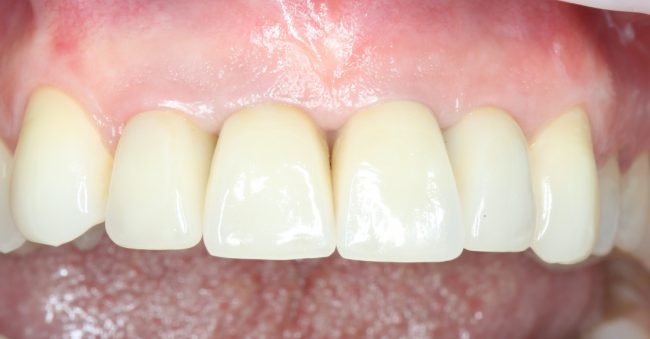

За фото не переживайте — эту пациентку мы вылечили))))